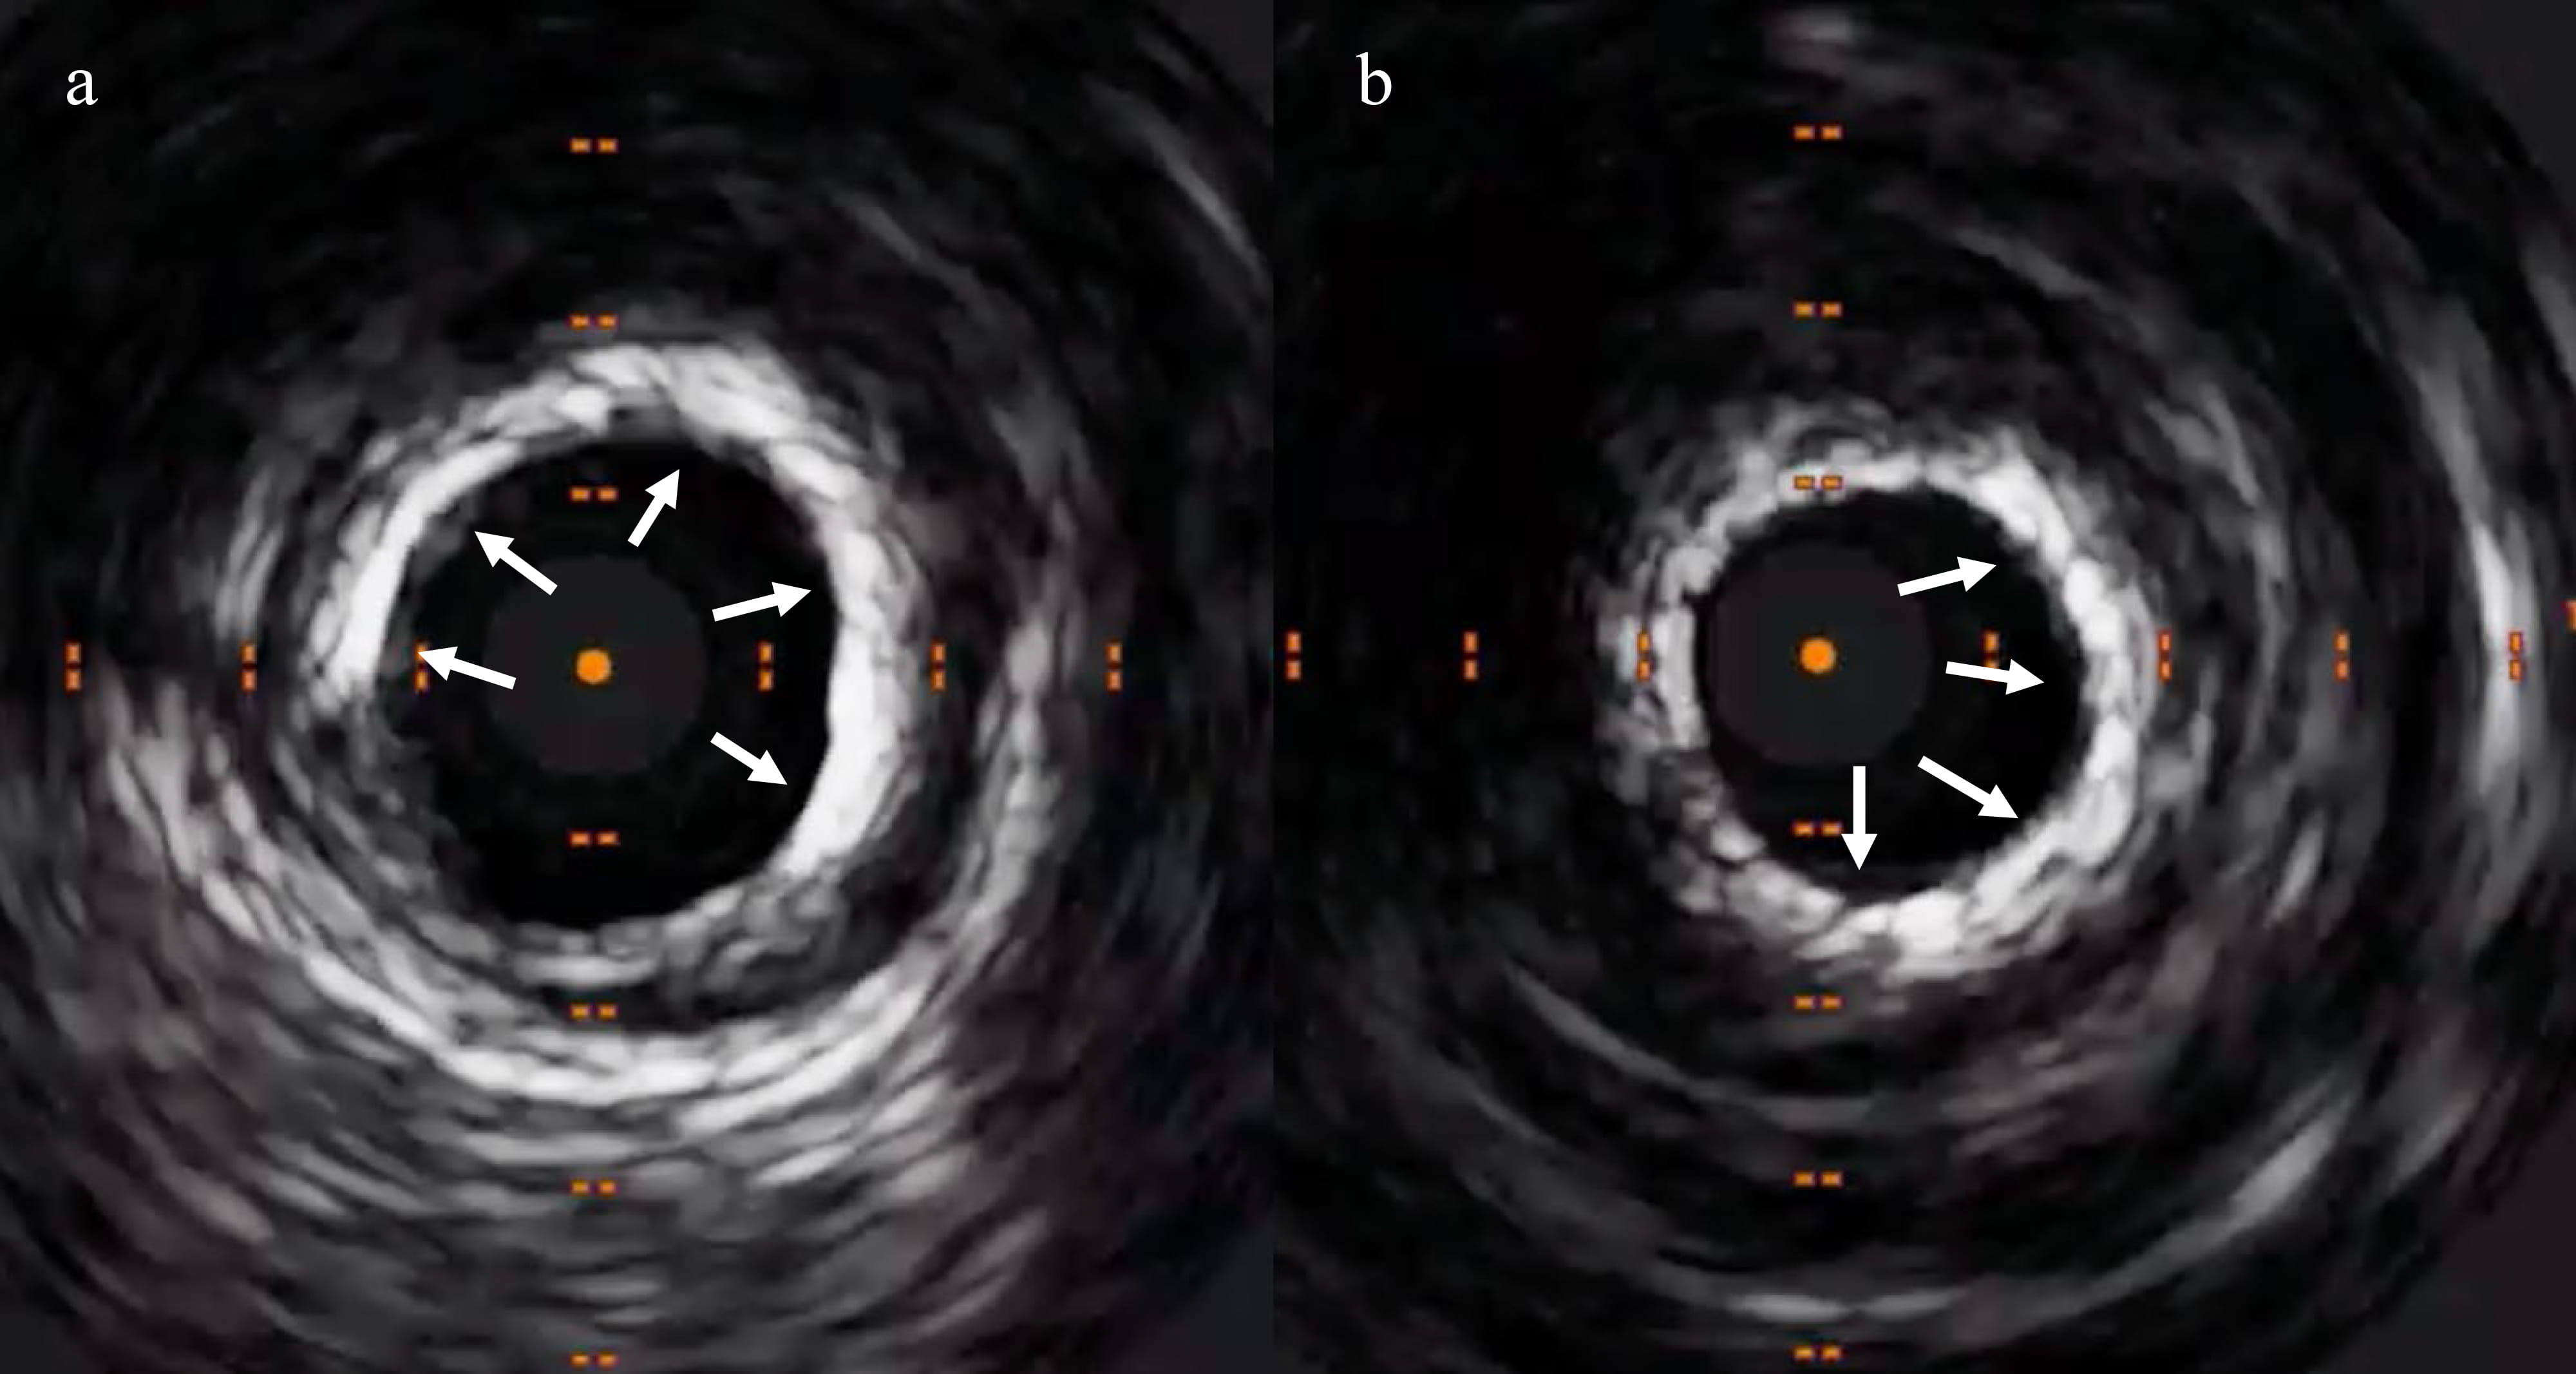

resulted in bursting of a 3.5 mm non-compliant balloon (Fig. 3). Intravascular

imaging visualised concentric calcium (Fig. 4). Subsequently, we used a 3.5 mm

Fig. 3.IVUS exhibiting concentric calcification at the site of lesion, which was not yielding. (a) Calcium arc extending from 9’o clock to 5’o clock positions (shown by the arrows). (b) Calcium arc extending from 1’o clock to 6’o clock positions (shown by the arrows).